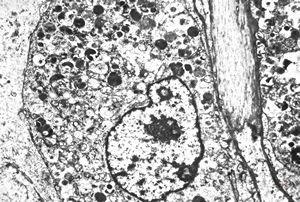

F, 24y. | molluscum contagiosum … virions

F, 24y. | molluscum contagiosum